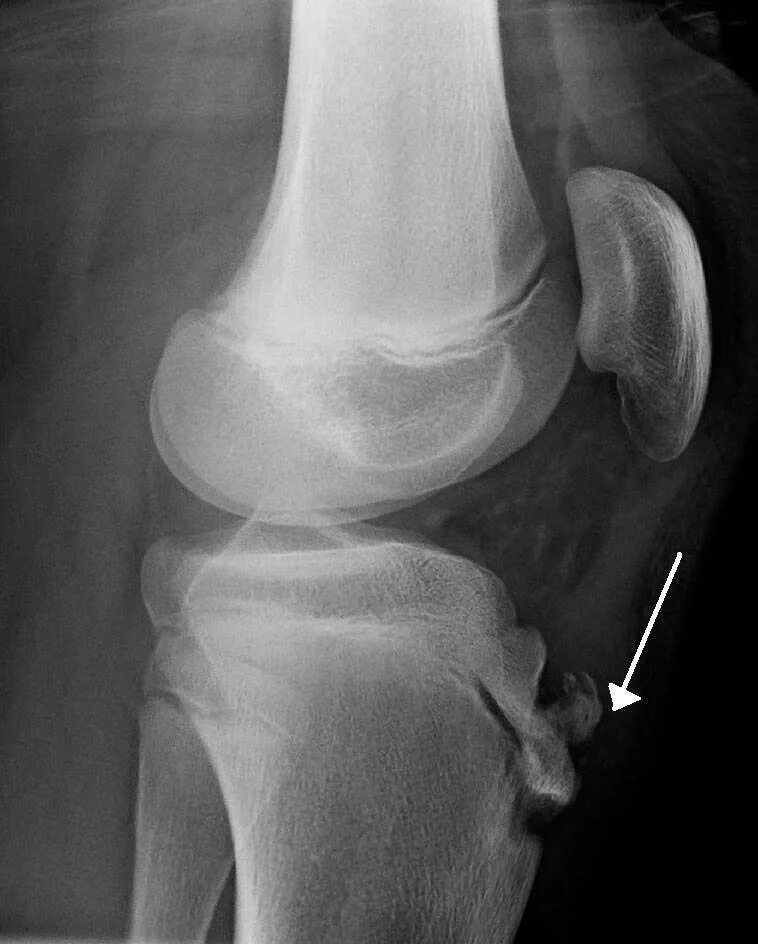

Код мкб шляттера